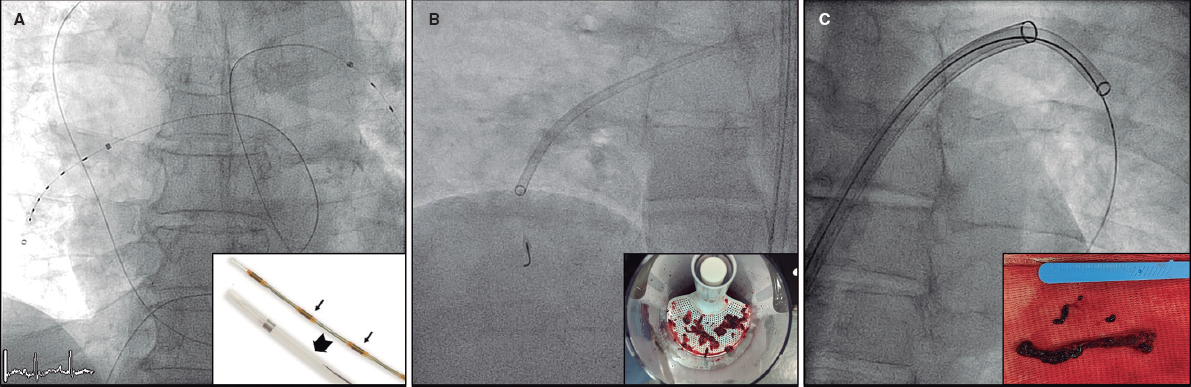

📌 Publicado en @RevEspCardiol. Experiencia inicial en TEP 🫁 con TDC en dos centros 🇪🇸. ✅ Uso creciente TDC ✅ TDC más frec en TEP bilateral, cirugía reciente y Charlson⬆️ 🚫 5% 🩸 IC fibrinolisis 🚫 10% complicaciones vasculares TDC @carlosreal42 @pabl0salinas Buen verano!